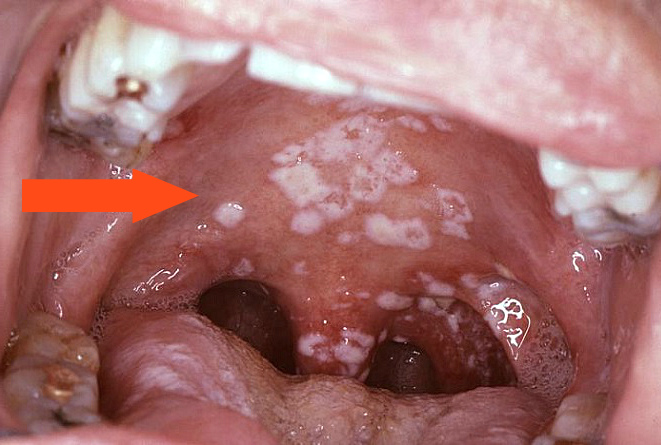

- Основным признаком является белый сырой налет в полости рта – на верхнем небе, миндалинах, внутренней стороне щек. Этот налет вызван грибами типа Candida, которые могут вызывать молочницу. Если налет имеет не белый, а желтоватый оттенок, и в очагах инфекции наблюдаются кровоточащие язвы, то это признак наличия плесневидных грибов в полости рта.

Грибковое заражение тканей горла может вызвать появление белого или желтого налета, который легко удаляется при полоскании горла или обработке антисептическим раствором, нанесенным на стерильный ватный тампон. Этот симптом важен, так как его проявления похожи на бактериальную активность во время развития заболевания, такого как дифтерия. Поэтому при обнаружении у пациента однородного налета на небе, миндалинах и в горле, врач назначает проведение дифференциального анализа для выявления грибкового агента.

- Фарингомикоз с псевдомембранозным проявлением. Патологическое состояние гортани характеризуется наличием на слизистой оболочке налета, имеющего белый, иногда бледно-жёлтый оттенок, и творожистую структуру. При удалении этого слоя обнажается ярко-красный эпителий, поверхность которого зачастую начинает кровоточить.

Часто люди путают истинный тонзилломикоз, когда белый или желтоватый налет появляется только на миндалинах, с фарингомикозом – заболеванием, при котором налет появляется на языке и на всей поверхности горла. Внизу приведено изображение ротовой полости при фарингомикозе.